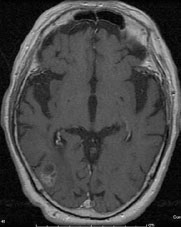

転移性脳腫瘍 肺癌の脳内転移

[ラジオサージャリー前]

CT(左画像): 左下の黒くなっているところが癌、 造影MR(右画像):左下の周りが白い線で囲まれたようになっているところが癌

[ラジオサージャリー後2ヵ月半]

CT、MRともに癌が縮小している。